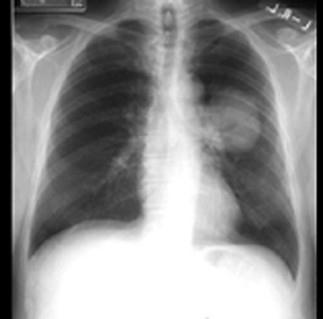

问题 既往健康的68岁男性患者,吸烟40年,因咳嗽,反复肺部感染,于门诊抗炎治疗近1年,胸部X线复查如图所示,形态不规则,边缘不整齐,收入院进 一步检查治疗。 经进一步检查,确诊为肺癌,首选治疗方案原则是 ( )

选项 A、中医中药治疗 B、手术治疗 C、放射治疗 D、对症处理 E、化疗

答案 B